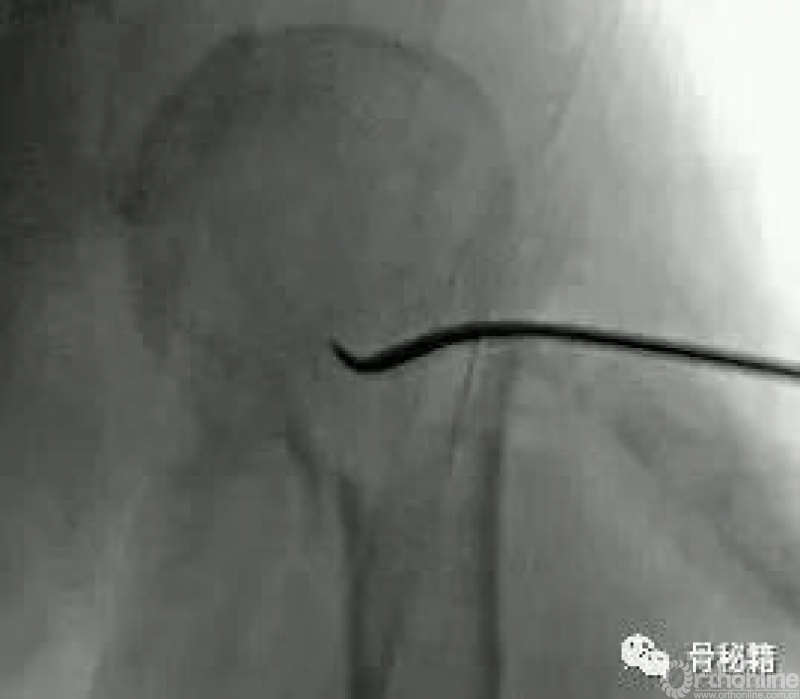

在复位好的基础上,植入合适的主钉导针

导针一旦植入,这个手术就完成了一半了